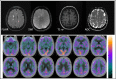

A case of anterograde amnesia in an MS-like demyelination after COVID-19